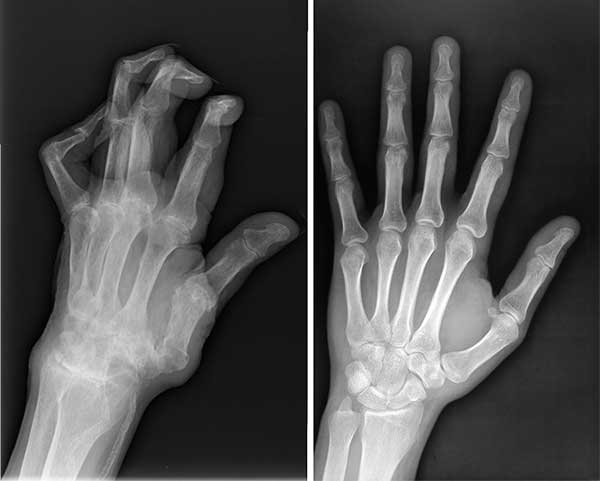

Rontgen suami sebelum dan sesudah mengonsumsi Megamove

Keadaan tangan suami saya sebelum dan sesudah mengonsumsi Megamove